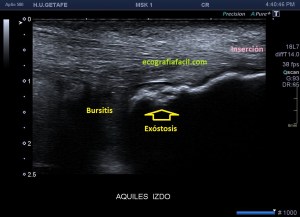

En el texto anterior hemos visto enmarañadamente muchos conceptos asociados a patologías que pueden darse en esta pequeña región del Aquiles. He nombrado el Síndrome de Haglund. Este es un síndrome que incluye tres aspectos, a nivel del aspecto posterior del calcáneo con una afectación de la bursa retroaquílea debido a la presencia de una exóstosis.

En muchas ocasiones vamos a encontrar calcificaciones de inserción o entensopatías, pero ver ecográficamente la afectación de la bursa es mucho menor. En muchas ocasiones, la radióloga necesita ampliaciones de estudio con radiología simple y con RMN para poder efectuar convenientemente este diagnóstico y nosotros, tenemos que ser muy minuciosos en la exploración ecográfica de esta región, conocer perfectamente ecoarquitectura normal de la región para poder identificar tanto los calcios insercionales como la bursitis retroaquílea, amén de la tendinopatía, ni que decir tiene a complicaciones tendinosas derivadas de estado avanzados de la patología como pudieran ser la roturas insercionales, parciales o totales.

Si observamos la bursitis retroaquílea de la imagen 11(flechas amarillas), además la exóstosis de la imagen 13 y deformidad en la piel, observable sin ecografía podemos estar ante un síndrome de Haglund de esos de libro…y tendremos una imagen ecográfica como la de la imagen 14.

Como has visto en la imagen 1, la bursa retroaquílea no debe verse, ese receso debe tener como mucho una mínima cantidad de líquido, que como digo es normal, pero no lo que observamos en la imagen 11 donde vemos una imagen heterogénea ocupando esa región.

La flecha amarilla indica la que en la parte posterior del calcáneo existe un calcio tosco en esta rx lateral del pie en carga, pero es en la inserción, cuidado con esto, cuando se produce el Haglund, no es en la inserción, es antes, y se debe a la exostosis mencionada con anterioridad, mira, compara imagen 12 e imagen 13. La flecha roja es indicativa de Síndrome de Haglund.

13

14

En la imagen 14, como no podía ser de otra manera, observamos todo y es por definición la típica imagen de S.Haglund.